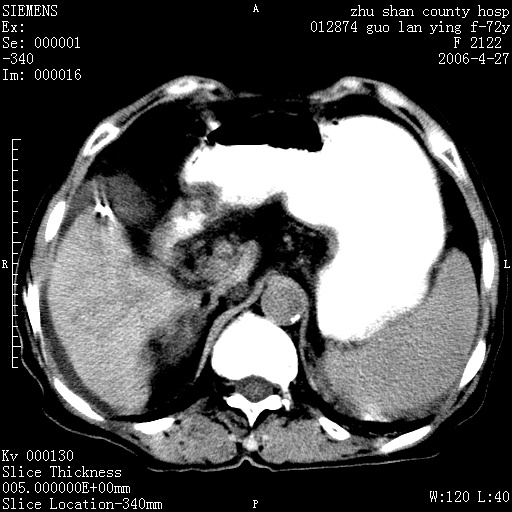

平扫所见:胆囊区两点壮高密度影,灶周有伪影{请问楼主患者有手术病史?}。肝实质内未见明显异常{建议强化或mri}.腹腔有少量积液,脾明显增大.右肾形态似不规则?

腹腔内示积液征,脾脏略增大,肝脏由于运动伪影较多,影响观察,内未见明显高密度区,胆囊内示两处高密度结石。胃窦部壁轻度增厚。另外,肝脏的前缘似有游历气体。不知病人的临床如何?有必要做胃的检查,还有,看看骨窗是否有腹腔游离气体还是肠管影响的。

肝脏缩小,脾脏增大,肝脾外缘及胆囊窝液性密度影,肝脾ct值正常,胆囊区见两个类圆形高密度影,下腔静脉前方类圆形软组织密度影为肝脏岛叶,胃幽门区见软组织密度影,十二指肠钡剂充盈不好.

1:腹水2:胆囊结石3肝硬化?(不确定,请结合临床)4幽门区占位?(建议胃肠透视)

肝硬化,脾大,少量腹水

肝硬化、腹水、脾大,胆囊结石可以肯定。只是肝右叶两个低密度有必要增强确定一下;排除小肝癌。